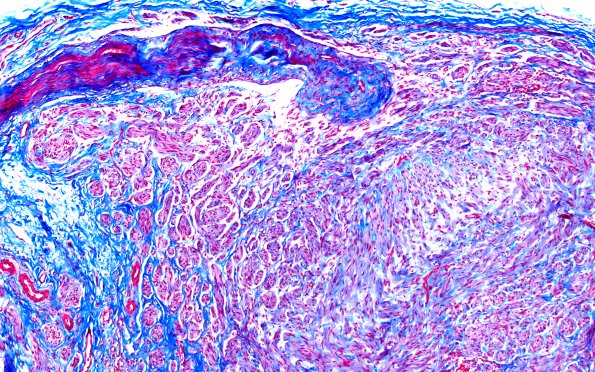

1E2 Neuroma, traumatic (Case 1) TRI 10X

1E2-4 Each mini-fascicle is surrounded by variable amounts of collagen. (Trichrome)